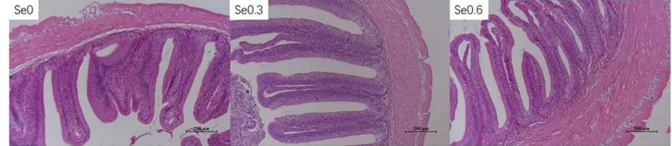

¾­¹ýÔ½¶¬ºóµÄ²ÝÓ㼫Ò׳öÏÖ³¦ÈÞë½á¹¹ÎÉÂÒ¡¢Î®Ëõ¡¢Õ³Á¬µÈ²¡ÀíÏÖÏ󣬲¿·Ö¼¡²ãºÍ½¬Ä¤²ãȱË𣨼ûÏÂͼSe0£©¡£ÔÚËÇÁÏÖÐÌí¼Ó0.3-0.6mg/kgÄÉÃ×Îø£¨ÒÔSe¼Æ£©ÄÜÏÔÖøÌá¸ß³¦ÈÞë¸ß¶È£¬¸ÄÉÆ³¦µÀ½¡¿µ×´¿ö£¨¼ûÏÂͼSe0.3ºÍSe0.6£©¡£